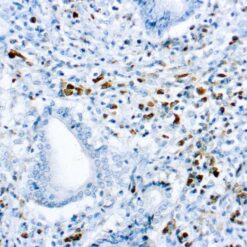

CD79a Antigen (HM47/A9)

This antibody is specific to human CD79a antigen complex, consisting of two polypeptides non-covalently associated with membrane-bound immunoglobulins on B cells. This complex of polypeptide and immunoglobulins constitute the B cell antigen receptor. The two components of this complex are designated CD79a and CD79b. The CD79a antigen appears at the pre-B cell stage, early in maturation and persists until the plasma cell stage. The CD79a antigen is found in majority of acute leukemias of precursor B cell type, in B cell lines and B cell lymphomas.

| Positive Control Tissue | Tonsil |